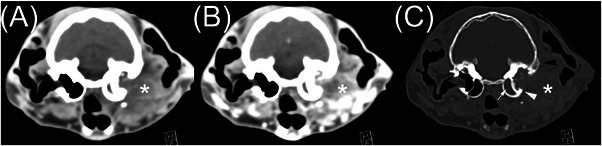

Computed tomography is commonly used to evaluate feline otic disease; however, published studies characterizing the CT appearance of ear canal neoplasia are limited. The purpose of this multicenter, retrospective, secondary analysis, cross-sectional study was to describe the CT features of histopathologically confirmed feline ear canal neoplasia. The CT studies of 25 cats with ear canal neoplasia were prospectively scored by consensus of two veterinary radiologists. Recorded parameters were the presence of focal or multifocal tissue enlargement (mass/masses), lesion shape, location of the center of mass, attenuation characteristics, features of contrast enhancement, involvement of otic structures, calvarial and brain changes, changes of nearby structures, and lymphadenopathy. There was a significant overlap of CT findings between cats with malignant ceruminous gland neoplasia, ceruminous gland adenoma, and squamous cell carcinoma (SCC). Ceruminous gland adenoma was typically homogeneous in attenuation with homogeneous contrast enhancement and no intralesional fluid accumulations (IFAs) or involvement of adjacent structures. In contrast, SCC consistently had heterogeneous attenuation, heterogeneous contrast enhancement, IFAs, and involvement/invasion of adjacent structures. Malignant ceruminous gland neoplasia had variable attenuation and pattern of contrast enhancement with occasional IFAs and occasional involvement/invasion of adjacent structures. Knowledge of these imaging features will inform the creation of prioritized differential diagnosis lists. However, a biopsy is required to confirm the diagnosis.